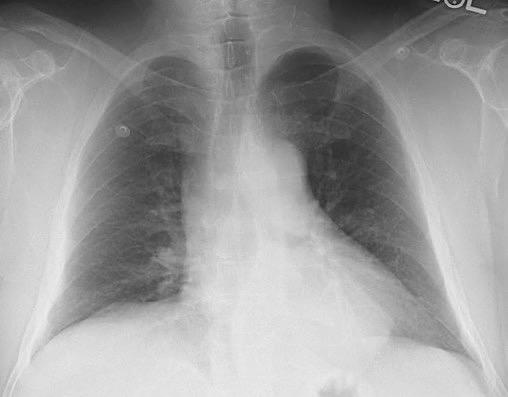

Nódulos pulmonares múltiples. (flechas verdes). Masas paratraqueales. (flechas amarillas). Dudoso ensanchamiento retrocrural (flechas negras). sigue….

T. mixto de células germinales del testículo

izquierdo Metástasis pulmonares. (flechas verdes). Ganglios paratraqueales. (flechas amarillas). Ganglios retroperitoneales (flechas negras)

T. mixto de células germinales del testículo izquierdo